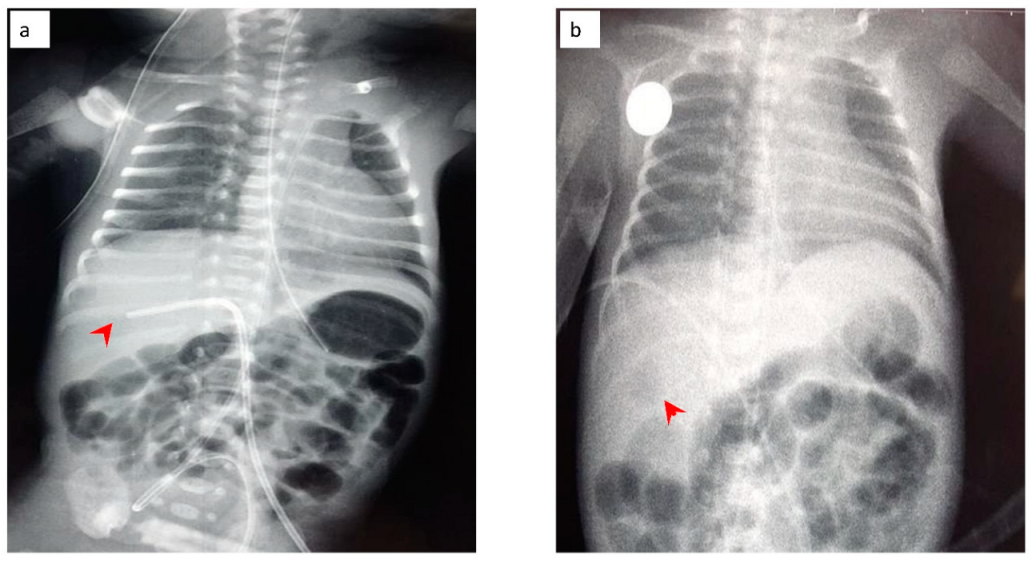

2.1. Case 1

2.2. Case 2

2.3. Case 3